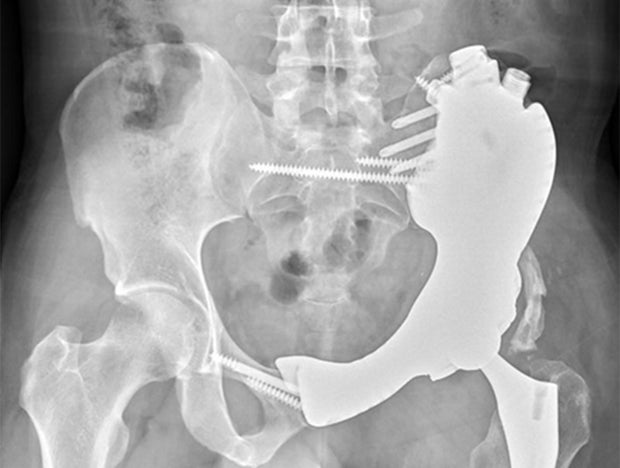

During his first meeting with Smith, Mesko outlined his plan. Instead of removing the pelvis, replacing it with cadaver bone, and rebuilding Smith’s hip joint so he might be able to use a prosthetic limb, he would 3D print an implant specifically fitted to the gap that would be left when the sarcoma was removed. It’s a process that has been done before, Mesko said, but it’s only become possible to do it regularly in the past decade. He estimated that about 500 to 1,000 such implants are used in a year in the U.S.

Mesko and his coworkers at the Cleveland Clinic “definitely do a lot of custom pelvis work with joint and tumor patients,” he said, estimating his team created about 20 custom implants in 2023.